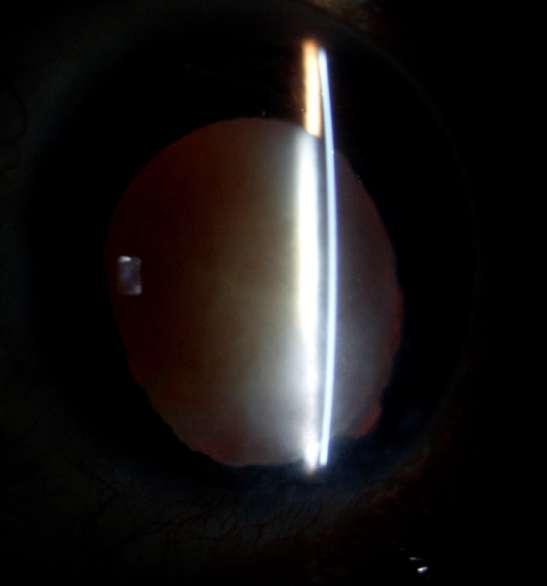

7.B. CATARATA LAMELAR

Imágenes aportadas por Dr. Álvaro Rodriguez

BAü La catarata lamelar también denominada zonular, es la más frecuente de las cataratas infantiles.

ü Se puede heredar en forma autosómica dominante.

ü Se presentan como opacidades bilaterales del núcleo y son el resultado de un daño al cristalino durante el desarrollo fetal siendo las capas más internas afectadas en mayor importancia mientras más precoz haya sido el daño.

ü Clínicamente se caracteriza por la presencia de opacidades en el cristalino que semejan protuberancias en forma de dedos proyectánddose a partir de un núcleo opacificado asociada con regiones de opacidad pulverulenta (Imagen A y B).